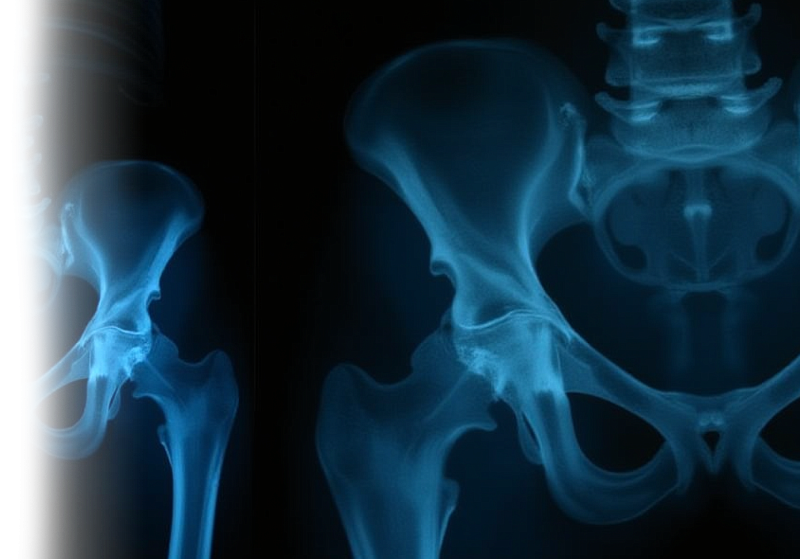

Компьютерная томография костей таза – важный метод прицельного исследования состояния костей таза.

Исследование позволяет оценить наличие костно-травматической, дегенеративной патологии костей таза.